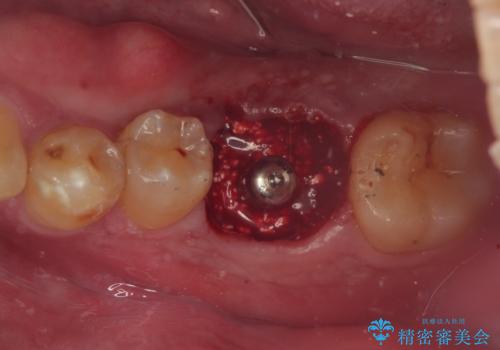

咬合力で破折した奥歯 抜歯即時埋入インプラントによる補綴治療

- 食事中に奥歯が痛むとのことで来院された患者様です。

レントゲンやCTより、深くまで破折していることが分かり、抜歯が必要な状態でした。

歯槽骨の状態は良好であったため、抜歯即時埋入インプラントによる補綴治療を行うこととしました。

インプラント埋入時に植立具合の安定性を測定したところ、十分な数値が得られたため、速やかに仮歯を装着して咬合回復をさせることができました。

抜歯を含めた外科処置を1回に抑えることができ、あっという間に治療を終えることができました。